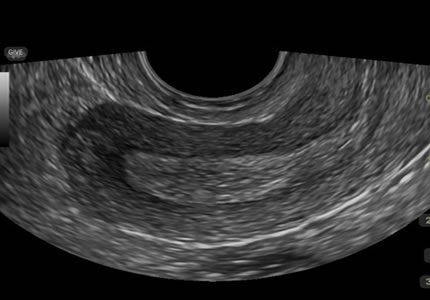

Comprehensive pelvic ultrasound evaluations for a wide range of non-pregnancy female health concerns, symptoms, or referrals.

Symptom-Based & Condition-Specific Scans